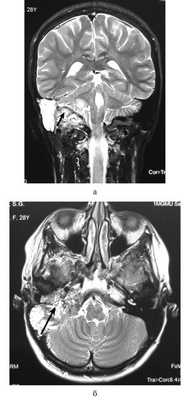

При опухоли типа, А в дообследование включали МСКТ височных костей, а также аудиологическое исследование. При большей распространенности новообразования (тип В, С, D) всем пациентам обязательно проводили МСКТ и МРТ височных костей с контрастированием. Пример МРТ представлен на рисунке.

МРТ основания черепа. Гломусная опухоль c распространением в заднюю черепную ямку (стрелки). а — коронарная проекция; б — аксиальная проекция.

В некоторых случаях для уточнения взаимоотношений новообразования с внутренней сонной артерией проводили КТ или МР-ангиографию. Также пациенты были консультированы неврологом, отоневрологом и нейрохирургом. При опухолях типа В, С, D за сутки до предполагаемой операции выполняли селективную эмболизацию сосудов, питающих новообразование.